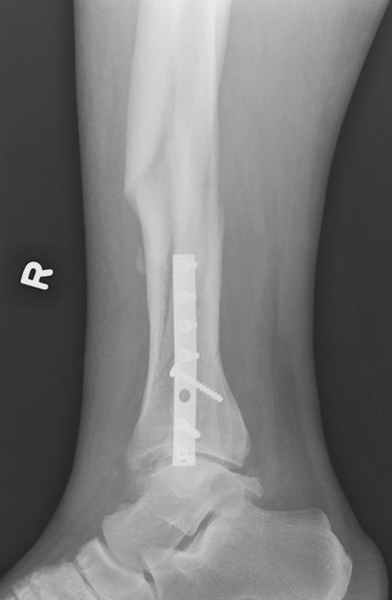

спрашивает что делать с больным который поступил недавно, фермер 55 лет падение при пьяной драке в баре, года два назад перенес операцию на лодыжке, на снимках и КТ перелом без вовлечения сустава,

Здесь мы использовали новый Synthes Nail с дополнительными дырками, в проксимальной части 4: по две косых и поперечные (один стандартный а другой динамический), в дистальной части две поперечные, прямая и косая. Вес больного более 120 кг, нагрузку начнем через месяц.

Получилось красиво, поздравляю. Вверху можно было ограничиться одним винтом во фронтальное статическое отверстие, зачем два 45-градусных?

При такий спирали задний край tibia может быть сломан - нет ли этого в данном случае? На всякий случай можно было ввести 1-2 винта 4,5 мм спереди назад мимо гвоздя. Хотя самый дистальный блокирующий винт, возможно, зацепил этот отломок. А какой тут диаметр гвоздя и locking винтов?